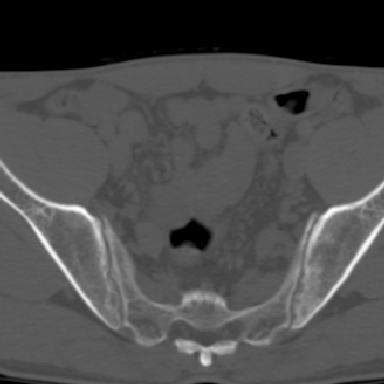

m 30 腰背部不适半年; 清晨时僵硬; 活动症状有所改善

双侧骶髂关节下2/3关节面模糊,毛糙,可见小囊状骨质破坏区.支持强直性脊柱炎.

强直性脊柱炎的早期改变!不仅表现为双侧骶髂关节,第5腰椎与骶椎间的关节突关节也有类似改变。

双侧骶髂关节下2/3关节面模糊,毛糙,髂骨侧可见小囊状骨质破坏区,骶髂关节间隙增宽(软骨破坏期)。支持早期强直性脊柱炎。

双侧骶髂关节下2/3关节面模糊、毛糙,可见小囊状骨质破坏区,呈虫咬状改变,周围可见增生硬化.支持强直性脊柱炎早期表现.

双侧骶髂关节髂骨面硬化,毛糙,小囊变,属于早期强直性脊柱炎